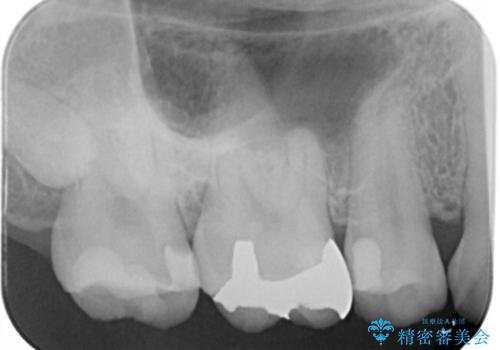

- 右上大臼歯の再治療を希望され来院された患者様です。

切削量と形状を考慮し、インレーでの治療を計画しました。

患者様がゴールドを希望されたのでゴールドインレーを選択しました。